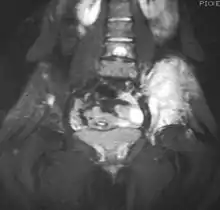

نتائج التصوير

على الأشعة التقليدية، العَرَض العظمي الأكثر شيوعًا هو الآفة نافذة التحلل مع تفاعل سمحاقي. والوصف الكلاسيكي للتفاعل السمحاقي مع هذه الآفة في شكل طبقات. تضيف الأفلام العادية معلومات قيمة في التقييم الأولي أو التحري. المنطقة الواسعة من الانتقال (على سبيل المثال: النفاذية) هي السمة الأكثر فائدة في الأشعة للتمييز بين الآفات الحميدة والخبيثة. ينبغي استخدام التصوير بالرنين المغناطيسي بشكل روتيني في فحص الأورام الخبيثة. فهي تُظهر كامل نطاق الأنسجة العظمية واللينة وتربط الورم إلى الهياكل التشريحية القريبة الأخرى (مثل الأوعية). تباين الغادولينيوم ليس ضروريًا لأنه لا يعطي معلومات إضافية عن الدراسات غير المتقابلة، على الرغم من جدال بعض الباحثين الحاليين بأن التصوير بالرنين المغناطيسي الديناميكي المعزز على النقيض من شأنه أن يساعد على تحديد مقدار النخر داخل الورم، وبالتالي يساعد في تحديد الاستجابة للعلاج قبل الجراحة.

يمكن أيضًا استخدام التصوير المقطعي المحوري لتحديد مدى خروج الورم عن العظام، وخاصة في الجمجمة والعمود الفقري والأضلاع والحوض. ويمكن استخدام كل من التصوير بالرنين المغناطيسي والتصوير المقطعي المحوري لمتابعة الاستجابة للإشعاع و أو العلاج الكيميائي. يمكن أيضًا استخدام تصوير العظام باستخدام الفطائر العظمية لمتابعة استجابة الورم للعلاج.